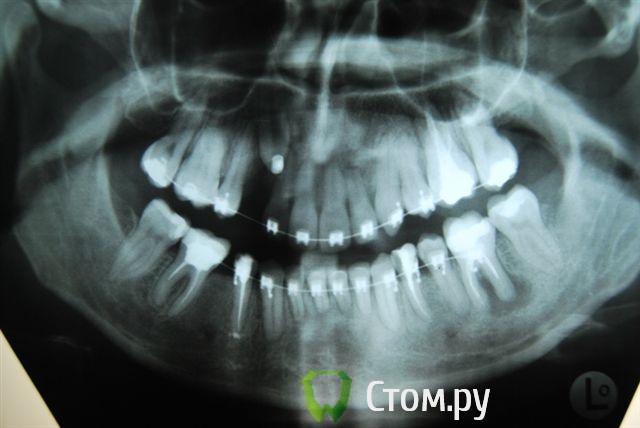

Александрстрад Опубликовано 8 ноября, 2011 Поделиться Опубликовано 8 ноября, 2011 Уважаемые доктора! Потерял и веру и надежду в возможность решения проблемы у своей жены. Одел на нее брекеты у знакомых ортодонтов в Москве, результаты, которых видел. В процессе лечения консультировался и ЦНИИСЕ у Арсениной и у других докторов, работал в крупнейшей медицинской компании, доступ к врачебной базе был очень большой. В процессе лечения все говорили что лечение идет нормально, а когда сняли брекеты ужаснулись все. Хронология лечения у ортодонта описана ниже, включая проблемы, которые мы получили после лечения.1. Показания к лечению брекет-системамиХруст при жевании в правом суставе.Замещение отсутствующего на нижней челюсти пятого зуба справа в течение 10 лет. В результате отсутствия 5-го зуба: наклон 4-го и 6-го по направлению друг к другу, резорбция (убыль) костной ткани на челюсти на месте отсутствующего зуба.Левый клык на верхней челюсти выходил из зубного ряда.Смешение центра верхней челюсти влево.Правый клык до момента начала лечения на верхней челюсти не вышел, находился в состоянии ретинированного, т.е. не вышел.2. Этапы леченияНачало лечения брекет системой - 2006 год.Снятие брекет системы 2009 год.Что было сделано:1. Левый клык на верхней челюсти был поставлен в зубной ряд.2. По отсутствующему 5-му зубу на нижней челюсти - доктор принял решение по замещению, путем передвижения зубов на нижней челюсти вправо,что и было проделано.3. Через 2 года ношения брекет-системы было принято решение по вытаскиванию левого ретинированного клыка.Был удален 3-ий зуб и в освободившееся пространство был вытянут клык.В результате данного объема работ и некорректной работы доктора,были завалены внутрь зубы на верхней челюсти - левая сторона, начиная от 1-го и далее, от резцов до жевательных.Также после сделанного панорамного снимка выяснилось, что произошло рассасывание корней 4-х фронтальных зубов на верхней челюсти более 65%.4. Также в процессе лечения был потерян 6-ой зуб на нижней челюсти слева. Проблемы сейчас1. Хруст в челюсти при жевании и зевании не прекратился, а появился и слева.2. Заваленная левая часть зубов на верхней челюсти не позволяет смещать нижнюю челюсть влево,тем самым перегружаются жевательные мышцы справа, в результате бывают головные боли и боли в мышце при жевании.3. Рассасывание 4-х верхних зубов.4. Расстояние справа между верхней и нижней челюстью на данные момент 3 мм. Сделали после снятия бректов исселдование у ортопеда, заключение ниже. Ее приговор - ТОТАЛЬНОЕ протезирование.Жене 36 лет, она даже слышать об этом не хочет. ПОМОГИТЕ РЕШИТЬ ПРОБЛЕМУ, НАДЕЖДЫ БОЛЬШЕ НЕТ. Заключение ОРТОПЕДАTreatment objectives∙ Transversal and sagittal discrepancy- make passive centic arch of upper jaw fit to active centric active lower jaw∙ First interference contact in RP on 24-34 and 37-27 with disocclusion for + 2 mm. Rp= 0=-2 mm, and till last contact =-4mm on incisal pin, so increase IP for =+3mm∙ Muscle problems∙ Change OPI on right side from 15 degrees to 20 degreees and change Cui right side to∙ Increse LFH +3 mm on incisal pin∙ Curve of Spee will be accentuated for 36∙ Steep condyle- decreased radius curve of Spee∙ Cui for 13 is not more than 55 degrees∙ Curve of Spee=Curve of wilson for 36 and 46∙ Rotation of mesial cusp of 6 down- change OPI for 36 – rotate 36 with mesial contact point OPI 6 = 35 degrees for DOA=12 degrees Ссылка на комментарий

Александрстрад Опубликовано 10 ноября, 2011 Автор Поделиться Опубликовано 10 ноября, 2011 Непонятны причины такой резорбции корней резцов...Да,задача номер один-стабилизация ВНЧС. Я бы пока не думал о повторном ортодонт.лечении,учитывая степень резорбции корней. По стабилизации - ортопед начала двигаться в этом направлении, для чего была проведена большая диагностика за 100 000 руб. в артикуляторе, сделаны слепки, снимки челюсти в госпитале МВД (описания делала сама начальник отделения, по отзывам одна из самых квалифицированных в Москве). После чего она вынесла решение по тотальному протезированию для нормализации положения суставов.Если будет возможность посмотреть презентацию с расчетами, которая была сделана и является финальным результатом диагности, готов отправить на почту. Был бы очень признателен.По тотальному протезированию - это катастрофа. Резорбция корней вызвана чрезмерной нагрузкой, в момент вытягивания правого ретинированного клыка. Когда его тянули резинки закрепляли за левую часть верхней челюсти, чтобы инициировать движение клыка, в результате и правую сторону челюсти "завалили" внутрь, а также получили огромную нагрузку на все фронтальные зубы, результатом чего и стала резорбция.Сначала доктор сам не поверил, что это произошло и может произойти в 33 года. Не рассматривался организм в целом при лечении и заболевания, а по факту у жены артрит/артроз. Ссылка на комментарий